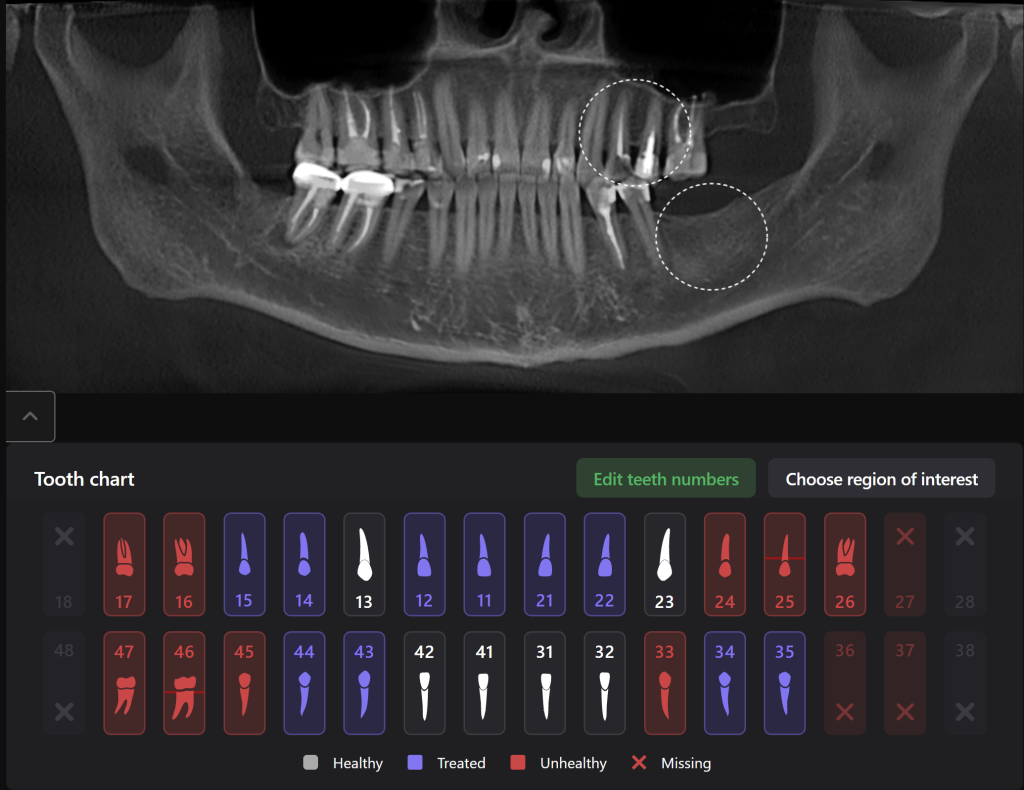

Planning implant placement using Diagnocat modules can help save the clinitian’s time and enhance the quality of implantological treatment

The result of collaboration with Diagnocat AI is a favorable outcome of the orthodontic and surgical stages of treatment